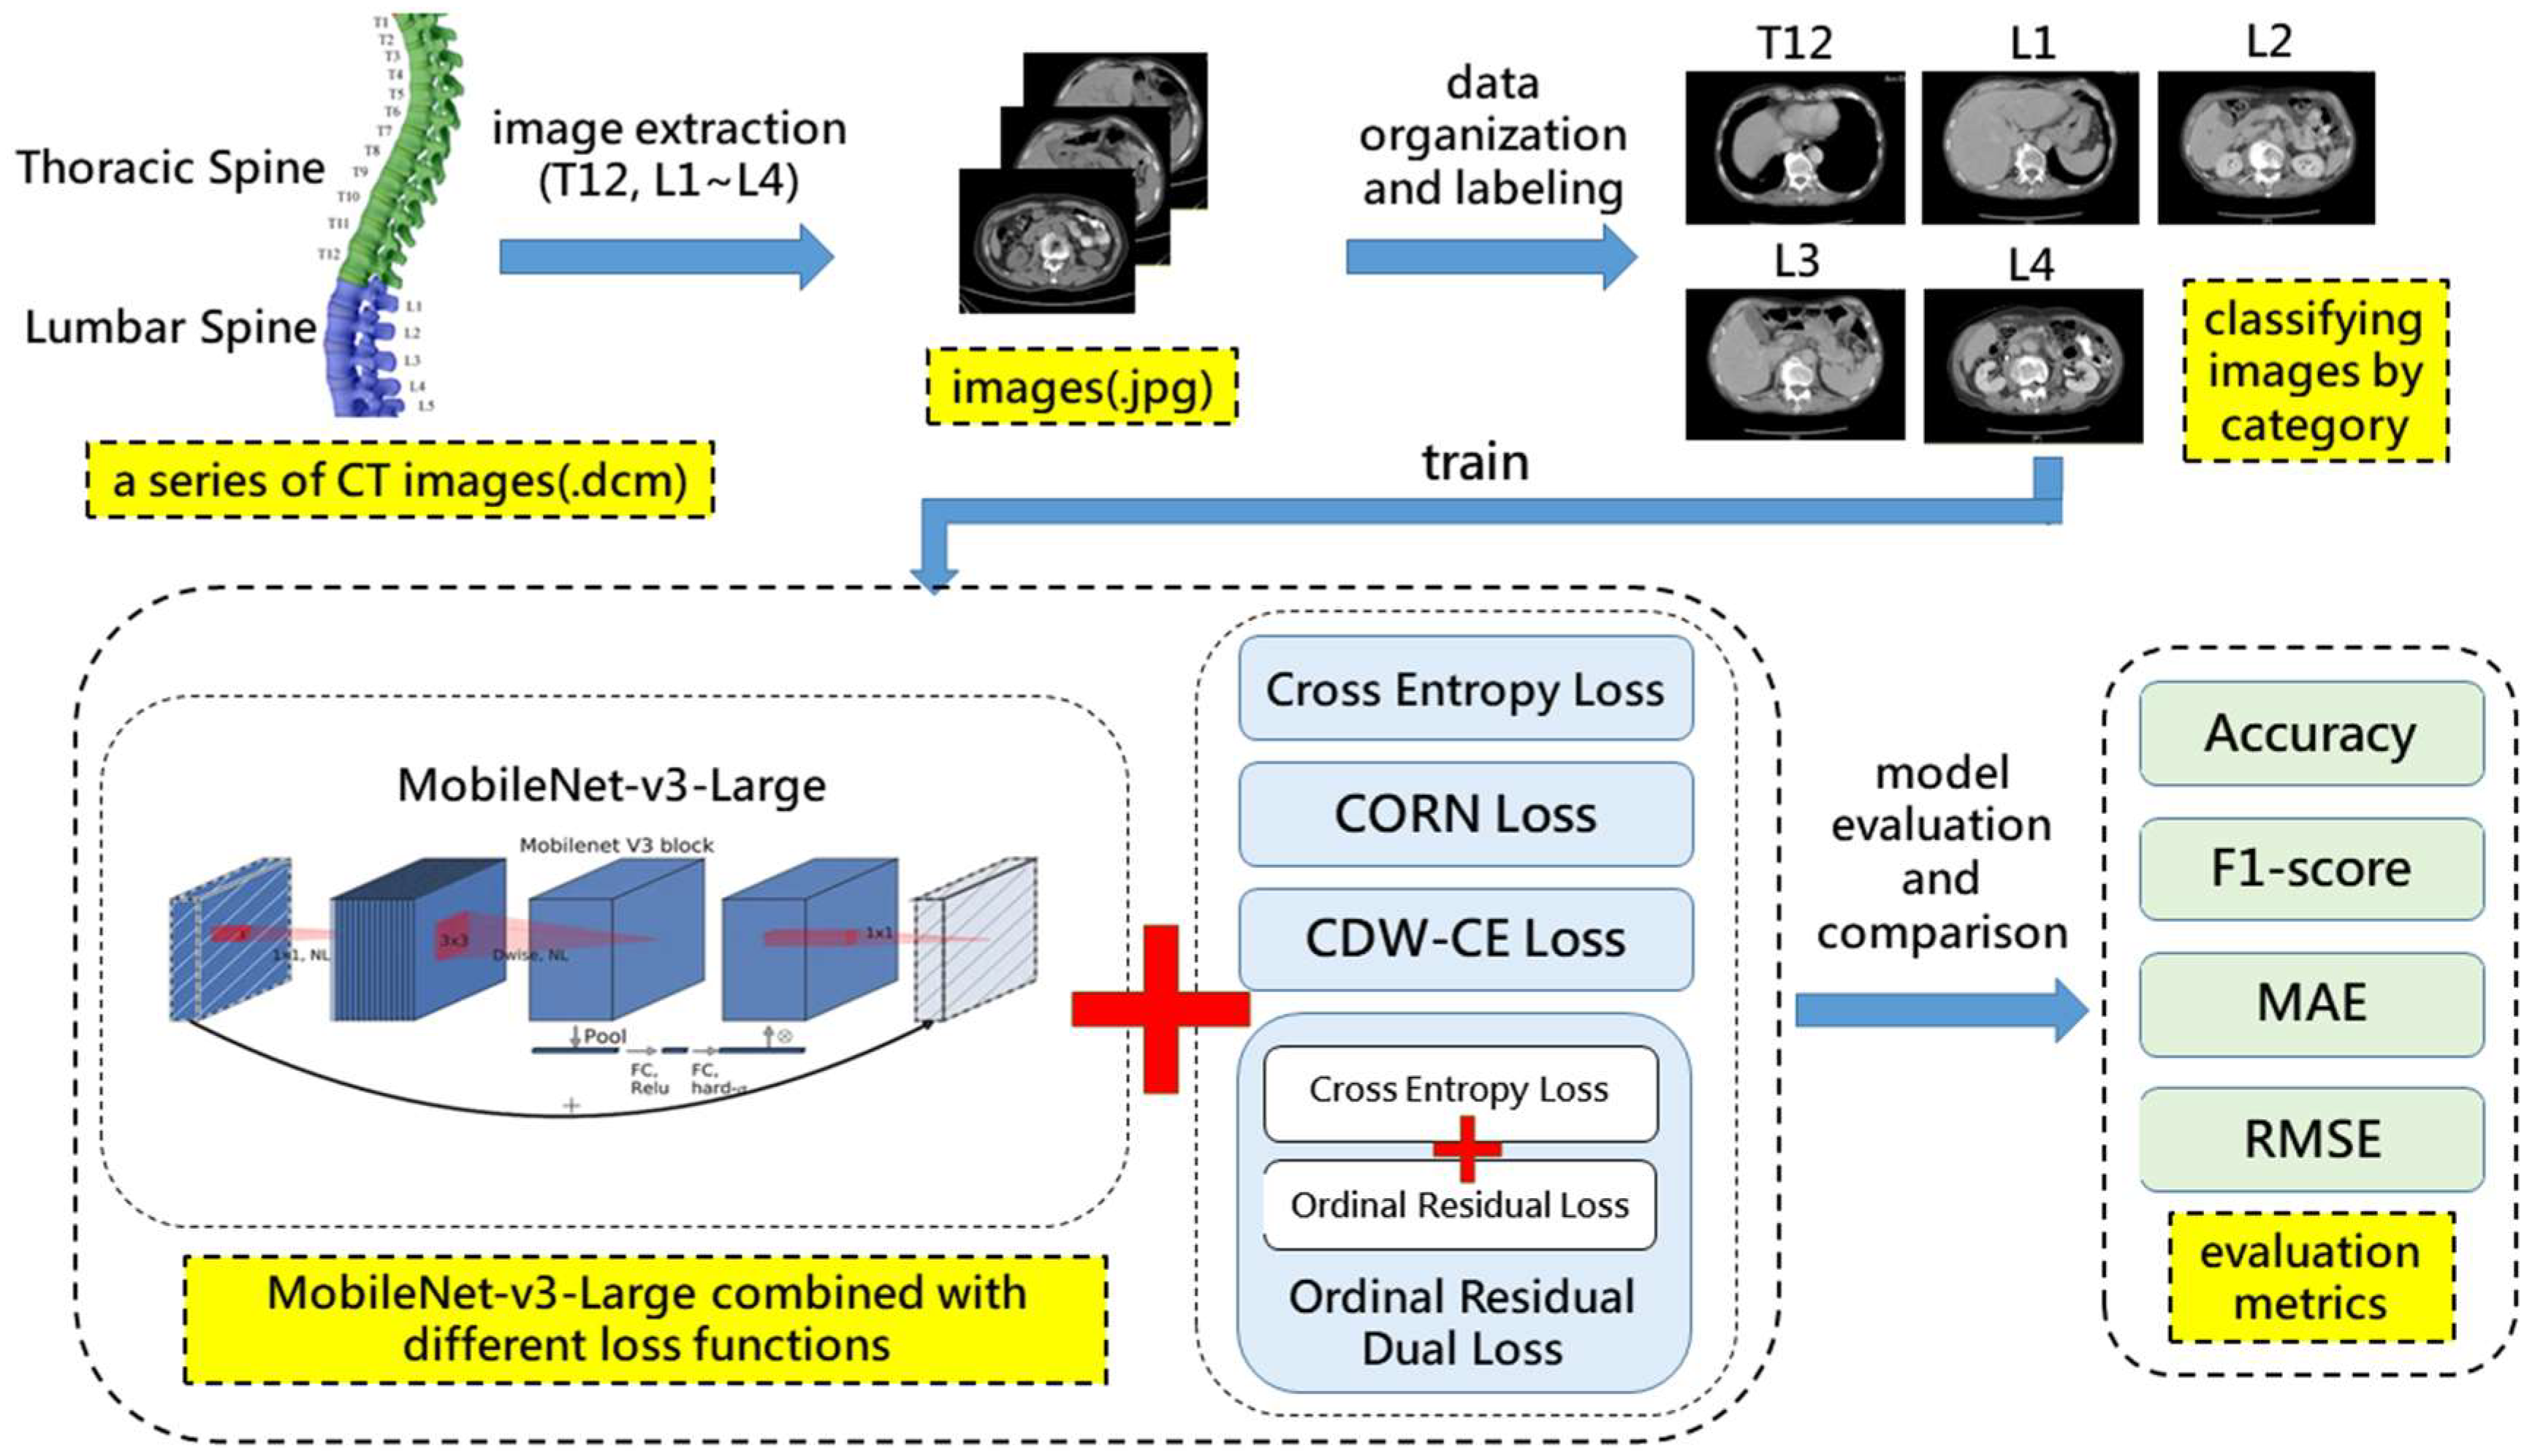

3. Materials and Methods

3.1. Research Framework

3.2. Ordinal Residual Dual Loss

3.3. CT Image Dataset

3.3.1. Dataset Description

3.3.2. Dataset Partitioning and Data Preprocessing